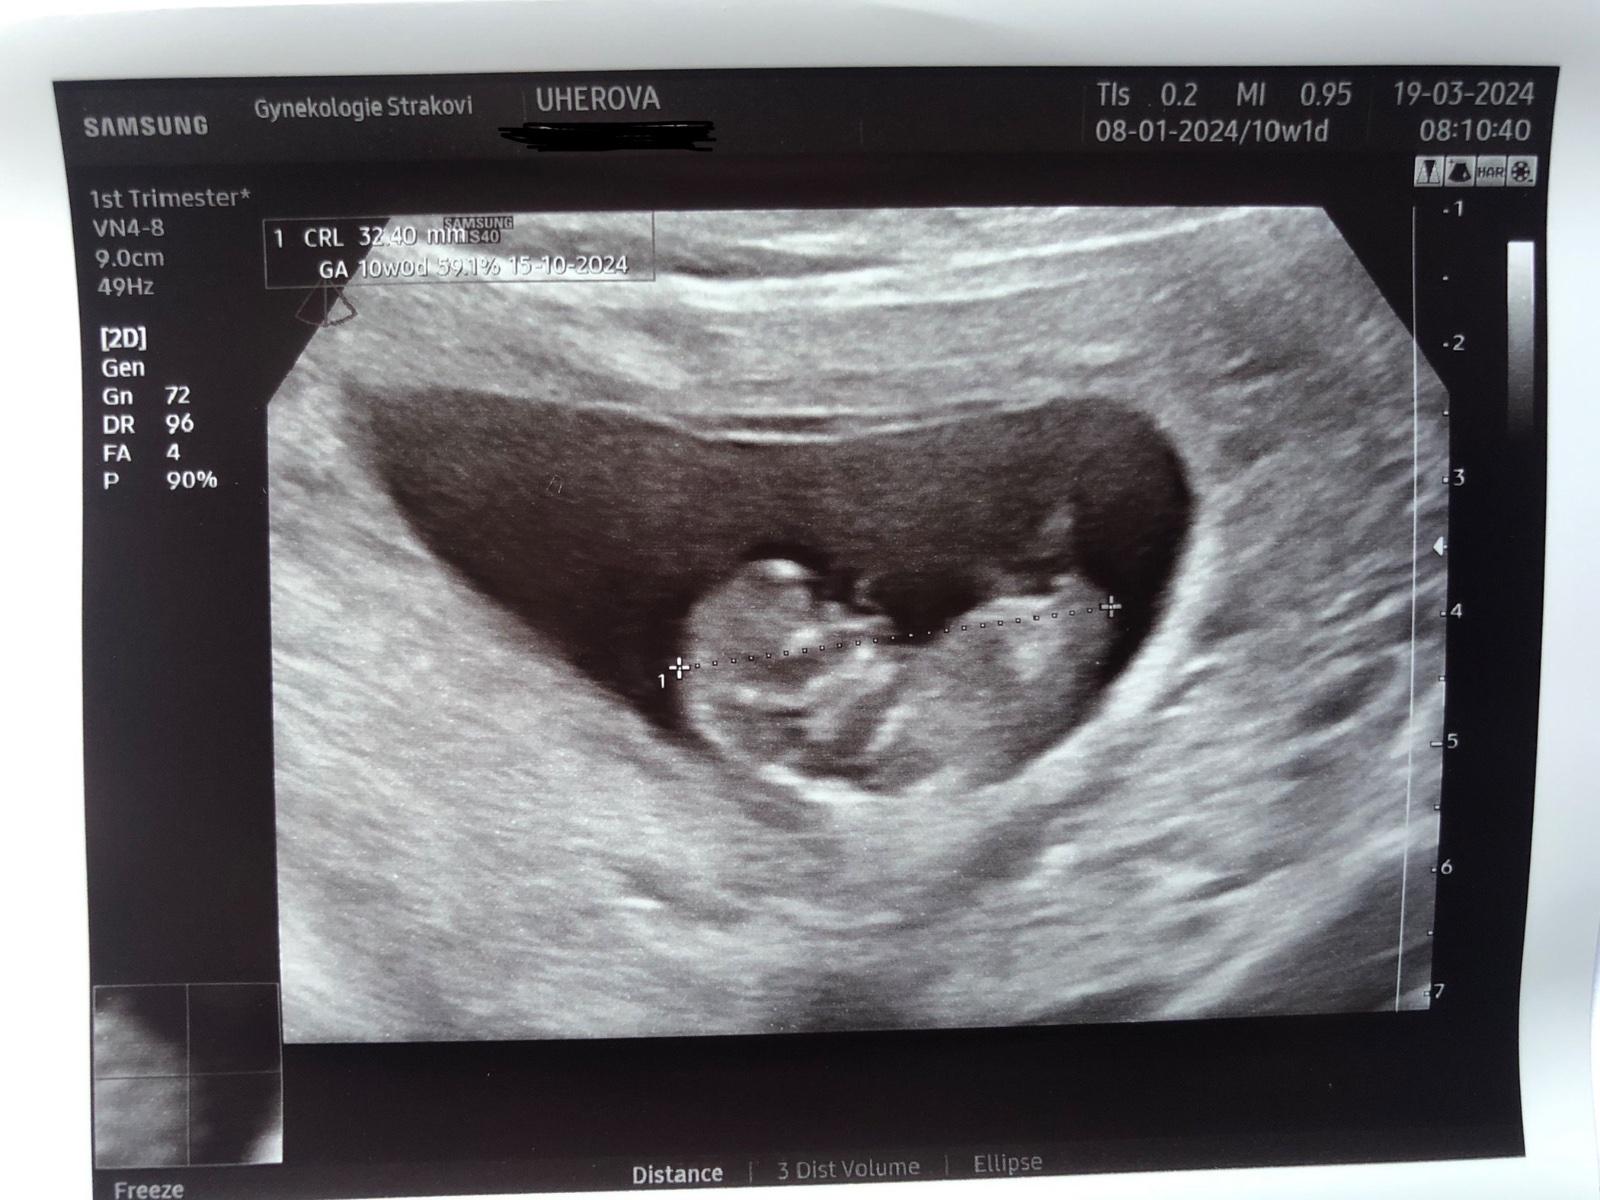

@aquenka tak holky, už mám po kontrole a to maličké pěkně roste dnes 10+1tt, malé odpovídá 10+0tt ❤️ a měří 3,2cm 🥹 na prvni screening jsem objednaná 9.4☺️